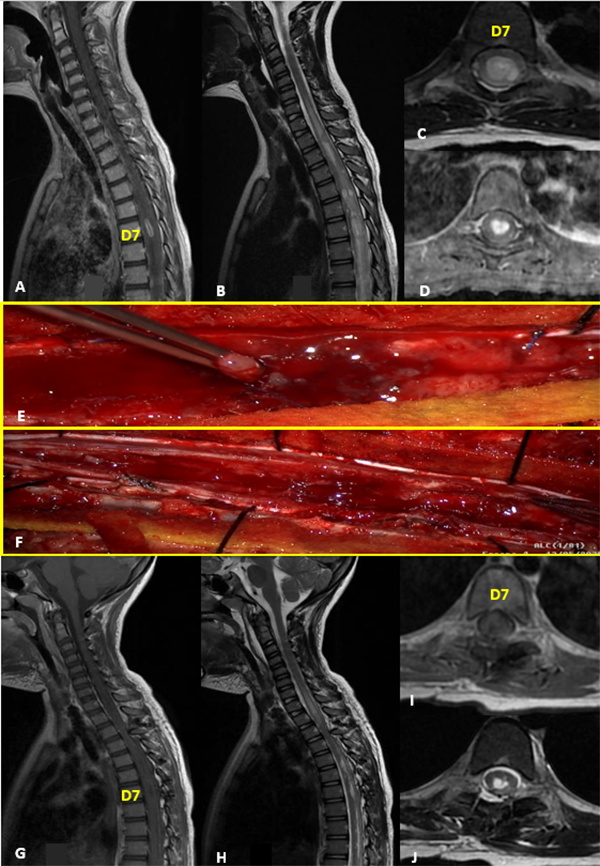

I: Ependimoma

Figura 1:

Ependimoma. A-D: RM prequirúrgica T1 con contraste y T2 cortes axiales y sagitales. E-F: Imágenes intraoperatoria pre y postresección. G-J: RM postquirúrgica T1 con contraste y T2 cortes axiales y sagitales.